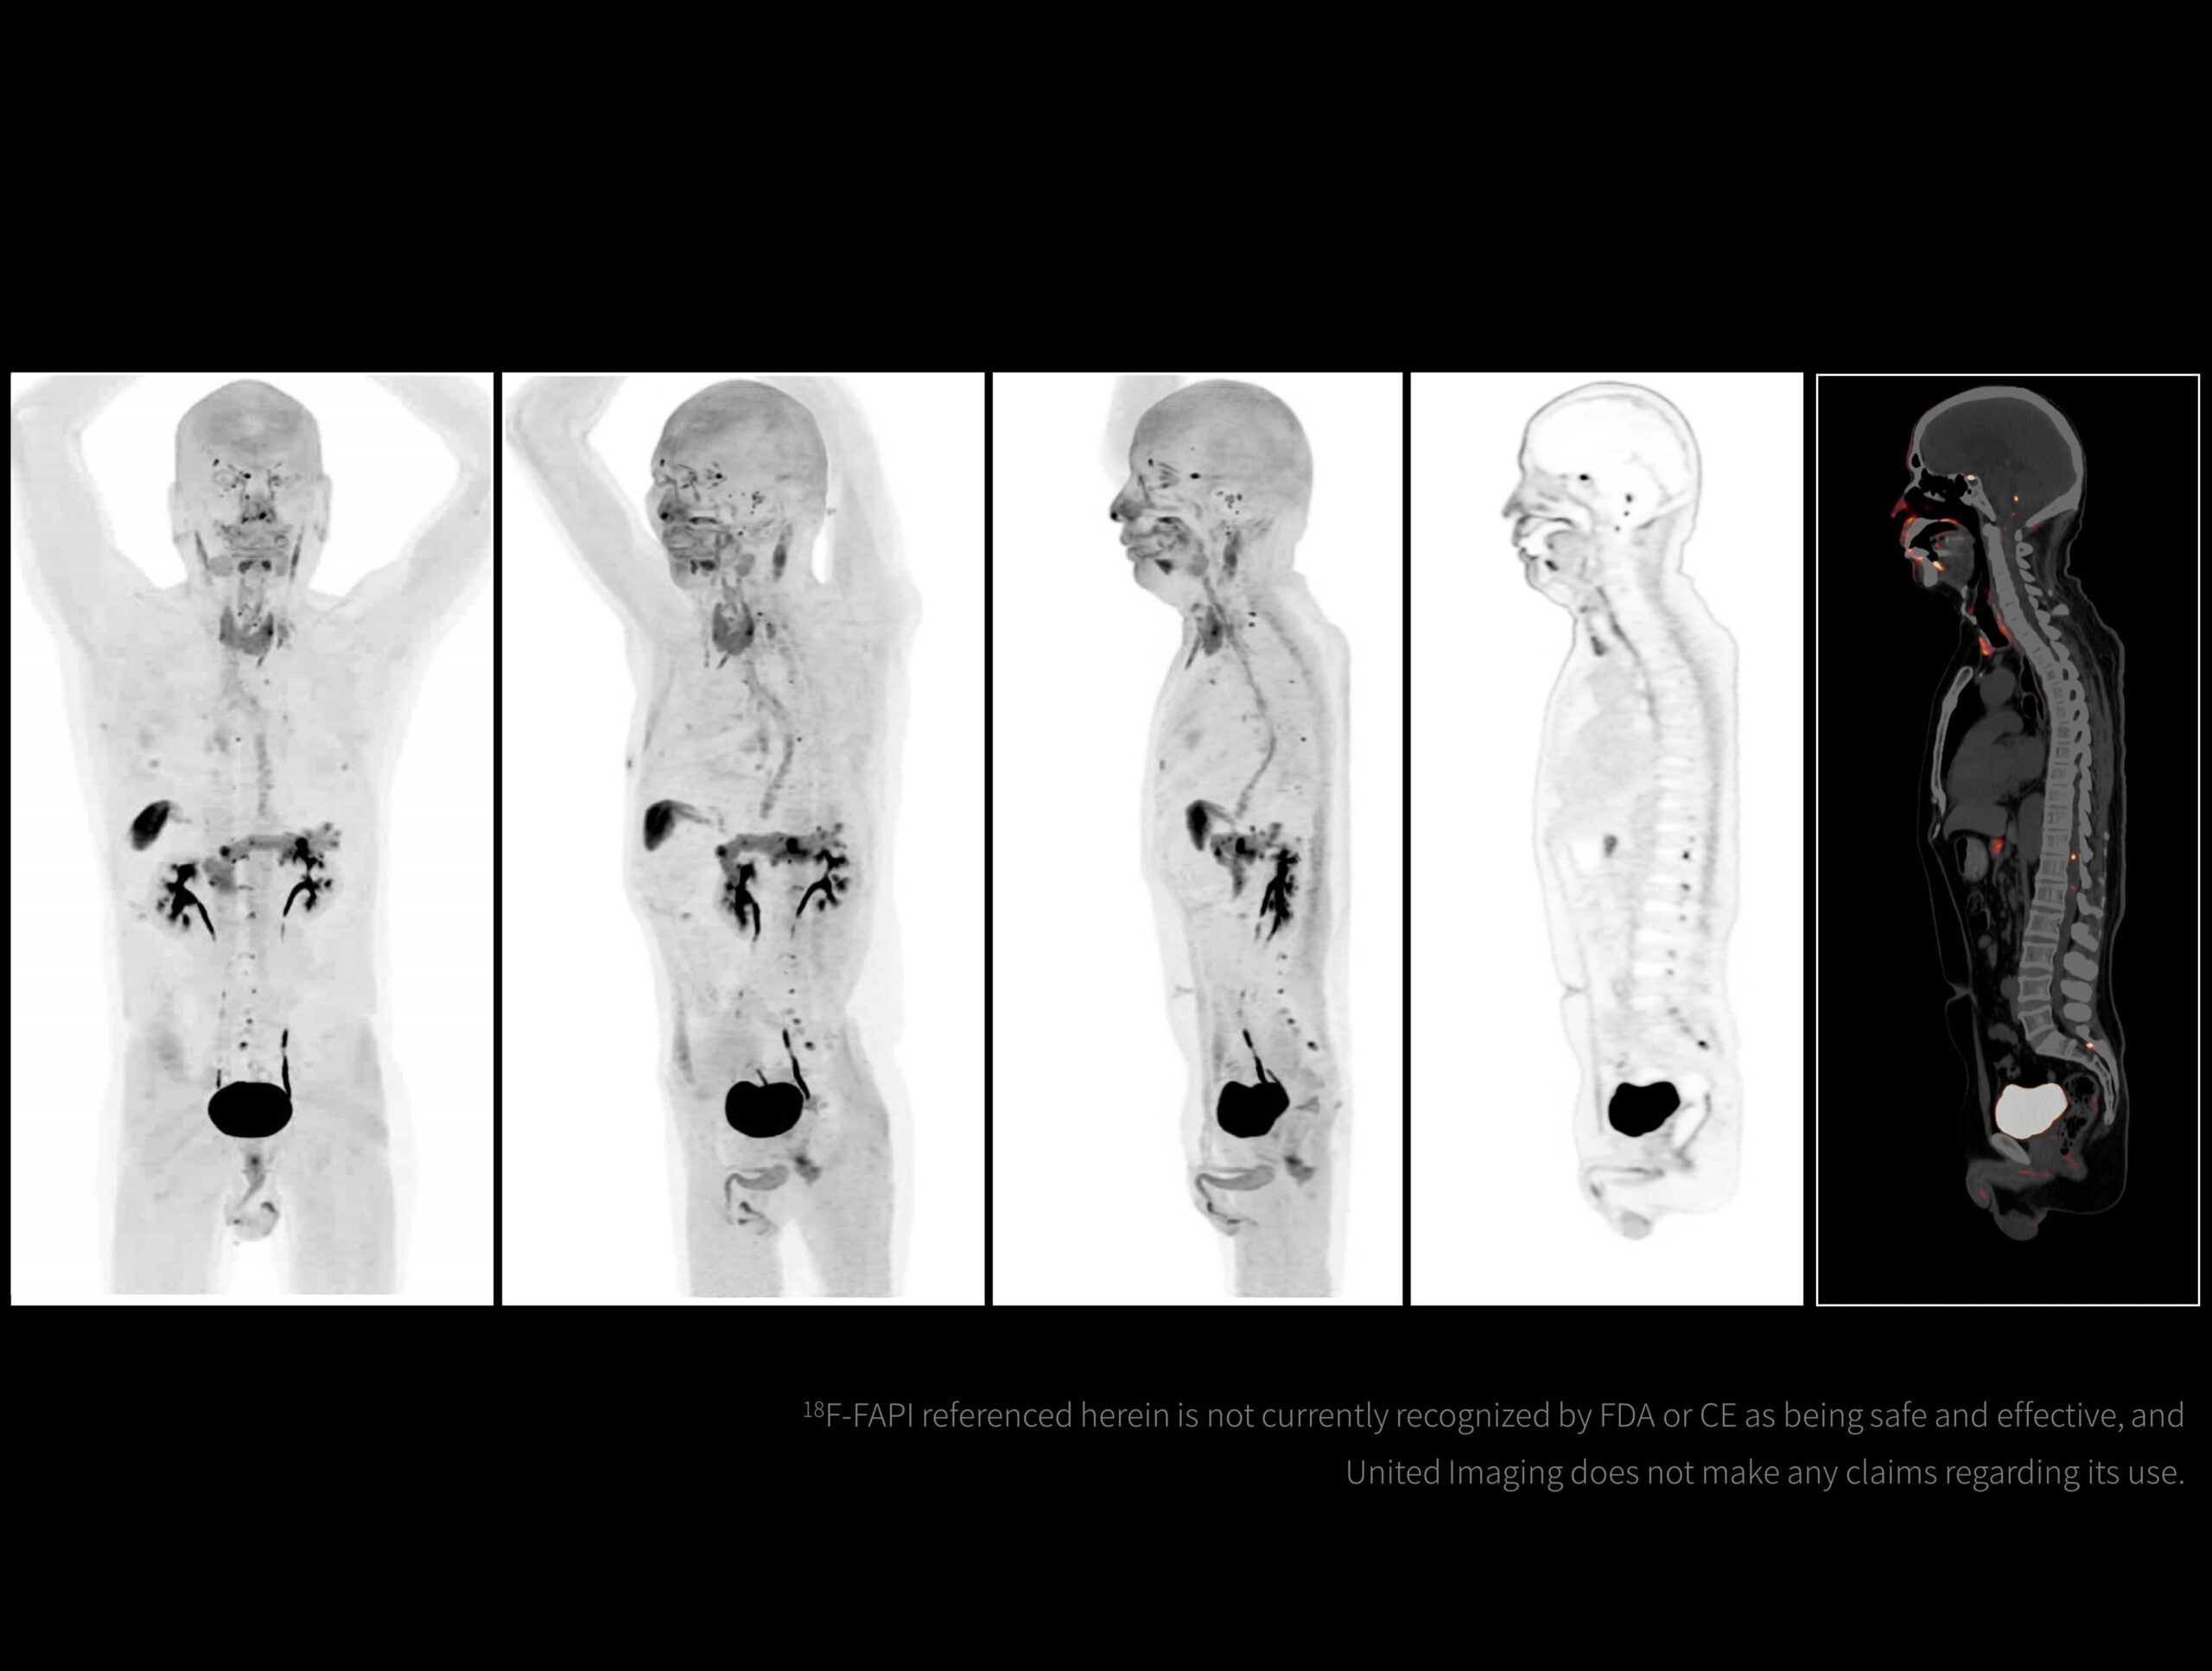

Cu o performanță ultra-înaltă, uMI Panorama face față provocărilor generate de radiotrasori cu diferite perioade de înjumătățire și de condiții complexe de scanare, menținând întotdeauna o calitate excepțională a imaginii.

Imagistică PET/CT cu noi radiotrasori